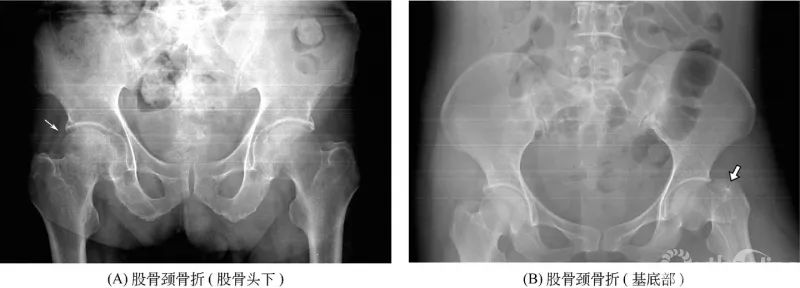

股骨颈骨折:(A)示右股骨颈短缩,皮质欠光滑,骨松质内见与股骨颈垂直的致密线影;(B)示左股骨颈基底部骨质断裂,股骨大转子上移,颈干角缩小。多见于老年人,骨折可发生于股骨头下、中部或基底部,断端常有错位或嵌入。